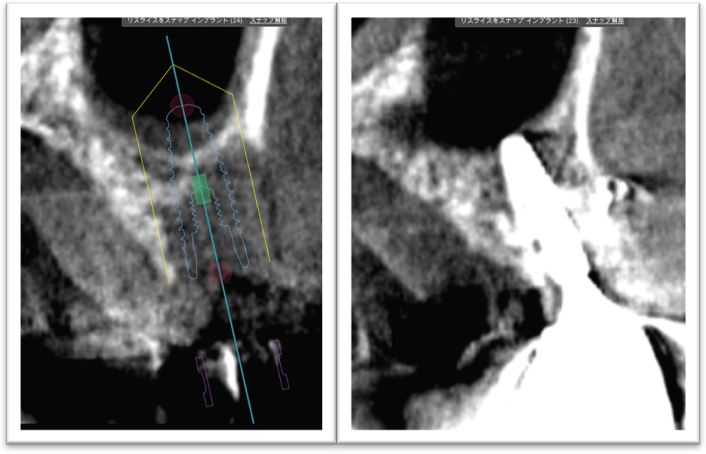

①歯槽頂よりサイナス

リフトを行いました。

②血液成分とカルシウム材料により骨造成をしました。

③ガイデッドサージェリーにてインプラント埋入しました。

④計画通りの埋入が出来ました。

術前ではインプラントを埋入する骨組織はほとんど有りませんが、

術後完全に骨内に埋入出来ました。